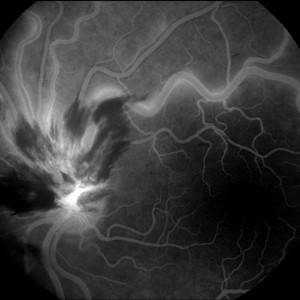

Hemizentralvenenverschluss (اختصارات و إقتصارات: Hemi-ZVV)

| الإنجليزية | hemi-central retinal vein obstruction (اختصارات و إقتصارات: HRVO, HCRVO) |